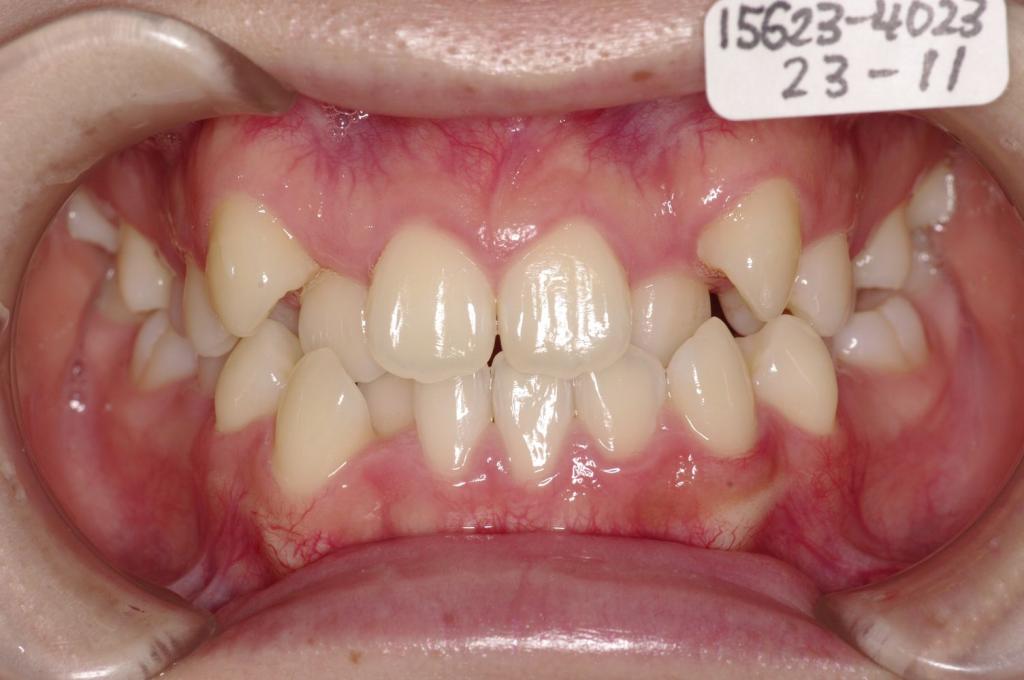

顎、顔の歪みの矯正治療

(治療期間、治療前後写真、治療方法、費用)WORKS